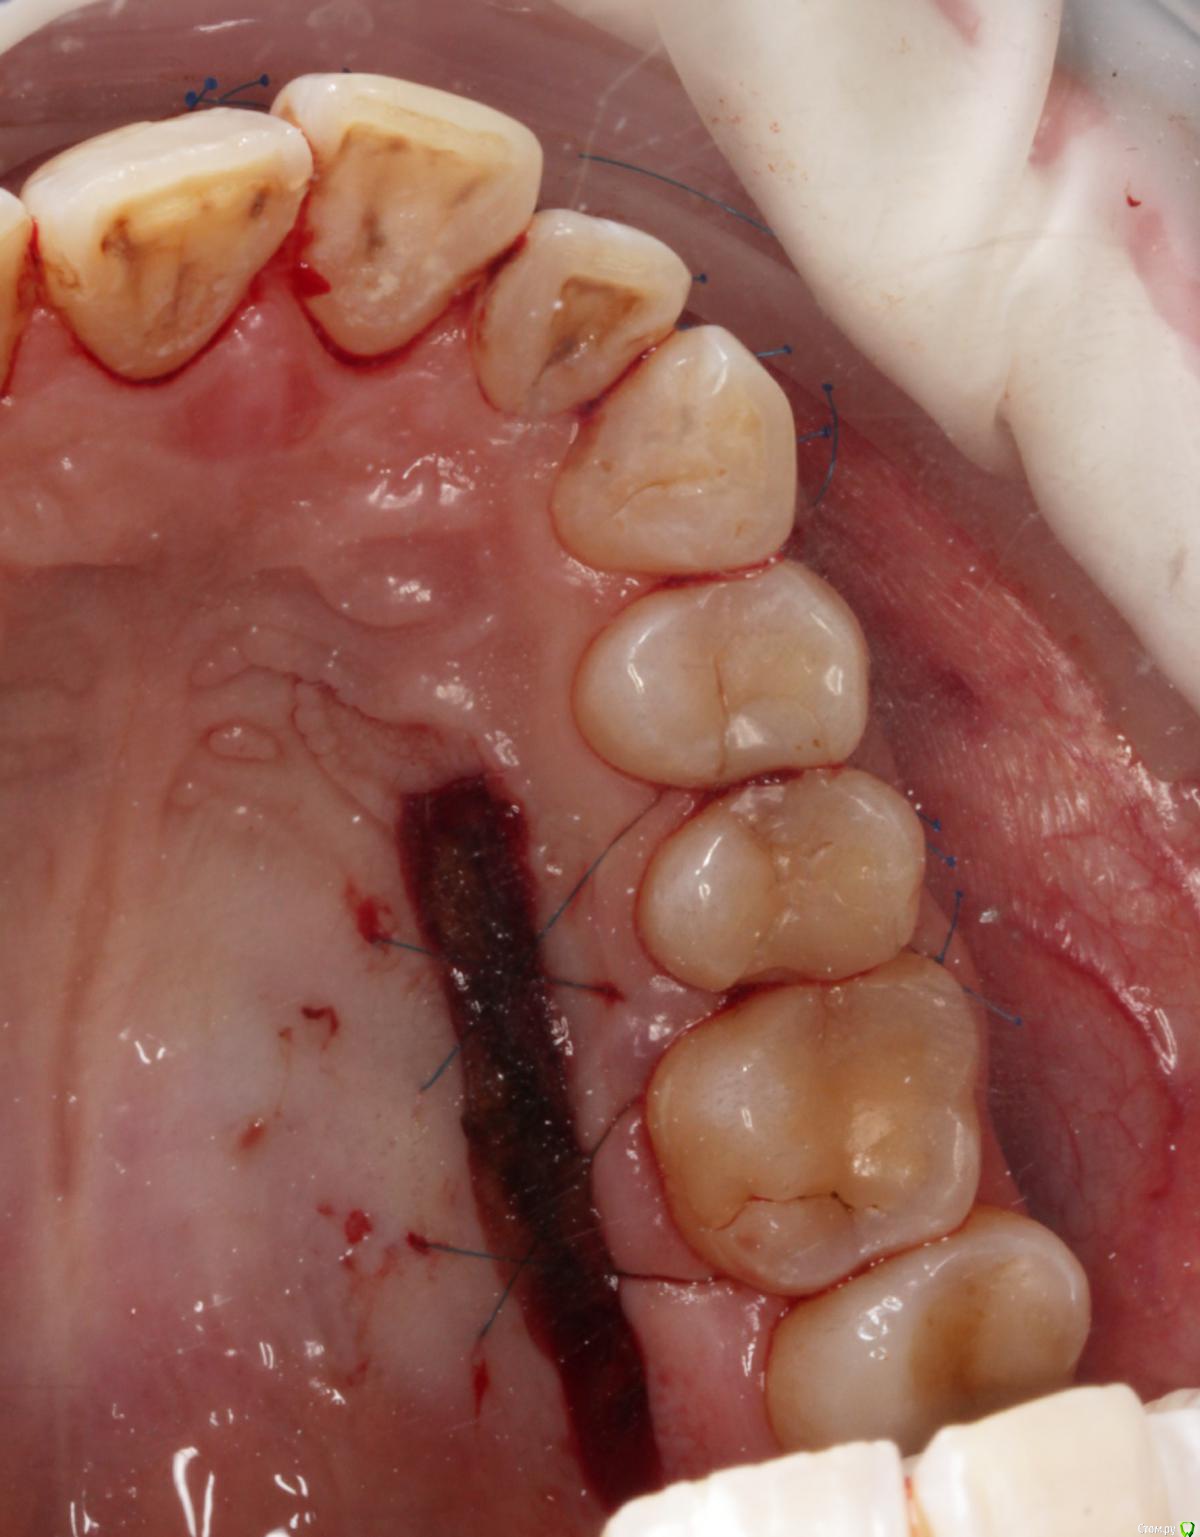

Amigo43 Опубликовано 3 сентября, 2019 Поделиться Опубликовано 3 сентября, 2019 Правильно ли я понимаю, что это штрауманн тл утопленный полированной шейкой в кость? Ссылка на комментарий

Dmitry DK Опубликовано 3 сентября, 2019 Автор Поделиться Опубликовано 3 сентября, 2019 Правильно ли я понимаю, что это штрауманн тл утопленный полированной шейкой в кость?да, это он Ссылка на комментарий

Dmitry DK Опубликовано 4 сентября, 2019 Автор Поделиться Опубликовано 4 сентября, 2019 короткий зуб, что же еще.У имплантата край дёсны действительно корональнее.Платплатформа в двух миллиметрах от цементо-эмалевой границы, была возможность иссечь излишек либо его ещё отдавить, также как хотелось заполировать в 1-м сегменте, поставит реставрацию на 21-м и т.д.Пациентка отказалась от дальнейших этапов... Ссылка на комментарий

Bier Опубликовано 4 сентября, 2019 Поделиться Опубликовано 4 сентября, 2019 так нужно было его просто глубже поставить Ссылка на комментарий

Dmitry DK Опубликовано 4 сентября, 2019 Автор Поделиться Опубликовано 4 сентября, 2019 так нужно было его просто глубже поставитьБыли такие мысли)Имплантат упёрся в нижнюю стенку синус. Весь винт с полированной частью 9,8 мм, шероховатая часть - 8 мм, от небной стеньки до синуса - 8 мм. Выбор был 1) закрытый синус, глубже платформа 2) выше платформа, без синусаВторой вариант выбран только по причине низких эстетических требований пациентки. 1 Ссылка на комментарий